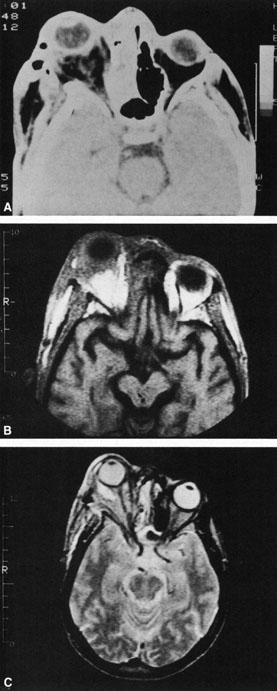

Rhinocerebral mucormycosis originates as a rhinitis, parapharyngitis, or sinusitis, and spreads by invasion of blood vessel walls, causing a necrotizing vasculitis with thrombosis of the vascular lumina and resultant infarction. The patient typically presents with unilateral orbital apex syndrome, including severe pain, visual loss, total ophthalmoplegia, corneal anesthesia, and multiple cranial nerve palsies.127 Orbital cellulitis presenting with early visual loss is one of the hallmarks of mucormycosis.72 Gangrene may occur of external periorbital tissues as well as of the hard palate and nose, and eschar-like crusting may be observed within the nose or on the hard palate (Fig. 23). Obstruction of the central retinal artery, ciliary arteries, and choroidal circulation can also be seen.124,125 Brain damage may occur because of spread of infection or infarction or occlusion of affected intracranial vessels.72

Fig. 23. Mucormycosis of the right ethmoidal sinus, with right orbital subperiosteal abscess formation. A. T1-weighted axial image. B. T2-weighted image. Note brain abscess.

CT shows sinusitis with or without bone destruction and is indistinguishable from other causes of orbital cellulitis.128 MRI may show carotid narrowing, occlusion, and absent flow in the superior ophthalmic vein (Fig. 24).72

Diagnosis is made by having a large index of suspicion and obtaining specimens of nasal turbinate, sinus, or infected orbital tissue. Large, branching nonseptate hyphae are readily apparent on hematoxylin and eosin staining or with methenamine silver staining (see Fig. 23). These hyphae can be grown on fungal culture.